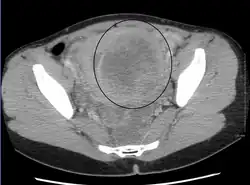

-

A very large (9 cm) fibroid of the uterus which is causing pelvic congestion syndrome as seen on CT -